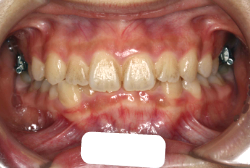

「歯並びの凸凹を直したい」という主訴で来院したケースです。診断の結果、たしかに「叢生」という隙間が足りないと言うことが原因の凸凹症例でした。

しかし、それ以上に問題なのは「前歯の噛み合い方が深すぎる」という症状で、初診の歯の正面写真を見ると下の前歯が全く見えません。こういう症状を矯正学では「過蓋咬合(かがいこうごう)」と言います。過蓋咬合を放置すると、将来的に顎関節に悪影響を与えるとされており、顎関節症の原因因子の一つです。また下の前歯の先端が、上の前歯の裏側の歯茎と強く接触するため、歯周病の原因にもなります。

検査の結果、凸凹が軽症なため非抜歯で矯正すること可能と判断、マルチブラケット装置にて治療しました。治療後は歯並びが綺麗になっただけでなく、噛み合わせ的にも正しい状態が確立しています。